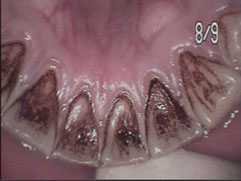

タバコのヤニがべったりついています。

タバコのヤニはしつこく、家庭での歯磨きでは落ちません。

PMTC(プロフェッショナルメカニカルティースクリーニングの略)という歯科医院専門の器具や特殊な研磨剤を使用しての研磨が必要です。

PMTCでその日の内にきれいになりました。(通常1~2日ですが状況によります。)

さらにPMTC後に、ホワイトニングを行ってもっと輝くような白い歯にすることもできます。